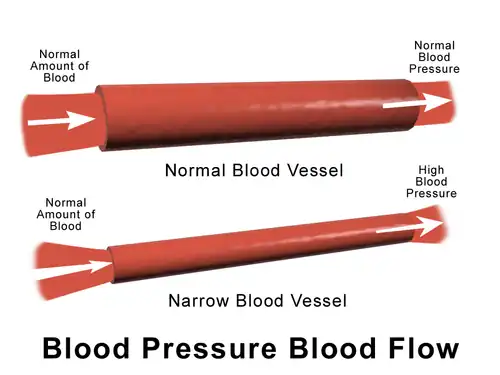

The larger arteries, including all large enough to see without magnification, are conduits with low vascular resistance (assuming no advanced atherosclerotic changes) with high flow rates that generate only small drops in pressure. The smaller arteries and arterioles have higher resistance, and confer the main blood pressure drop across major arteries to capillaries in the circulatory system.

In the arterioles blood pressure is lower than in the major arteries. This is due to bifurcations, which cause a drop in pressure. The more bifurcations, the higher the total cross-sectional area, therefore the pressure across the surface drops. This is why the arterioles have the highest pressure-drop. The pressure drop of the arterioles is the product of flow rate and resistance: ∆P=Q xresistance. The high resistance observed in the arterioles, which factor largely in the ∆P is a result of a smaller radius of about 30 μm.[24] The smaller the radius of a tube, the larger the resistance to fluid flow.

Substances called vasoconstrictors can reduce the size of blood vessels, thereby increasing blood pressure. Vasodilators (such as nitroglycerin) increase the size of blood vessels, thereby decreasing arterial pressure.

If the blood viscosity increases (gets thicker), the result is an increase in arterial pressure. Certain medical conditions can change the viscosity of the blood. For instance, anemia (low red blood cell concentration) reduces viscosity, whereas increased red blood cell concentration increases viscosity. It had been thought that aspirin and related "blood thinner" drugs decreased the viscosity of blood, but instead studies found that they act by reducing the tendency of the blood to clot.[26]

The ideal blood pressure in the brachial artery, where standard blood pressure cuffs measure pressure, is <120/80 mmHg. Other major arteries have similar levels of blood pressure recordings indicating very low disparities among major arteries. In the innominate artery, the average reading is 110/70 mmHg, the right subclavian artery averages 120/80 and the abdominal aorta is 110/70 mmHg.[25] The relatively uniform pressure in the arteries indicate that these blood vessels act as a pressure reservoir for fluids that are transported within them.

Pressure drops gradually as blood flows from the major arteries, through the arterioles, the capillaries until blood is pushed up back into the heart via the venules, the veins through the vena cava with the help of the muscles. At any given pressure drop, the flow rate is determined by the resistance to the blood flow. In the arteries, with the absence of diseases, there is very little or no resistance to blood. The vessel diameter is the most principal determinant to control resistance. Compared to other smaller vessels in the body, the artery has a much bigger diameter (4 mm), therefore the resistance is low.[25]